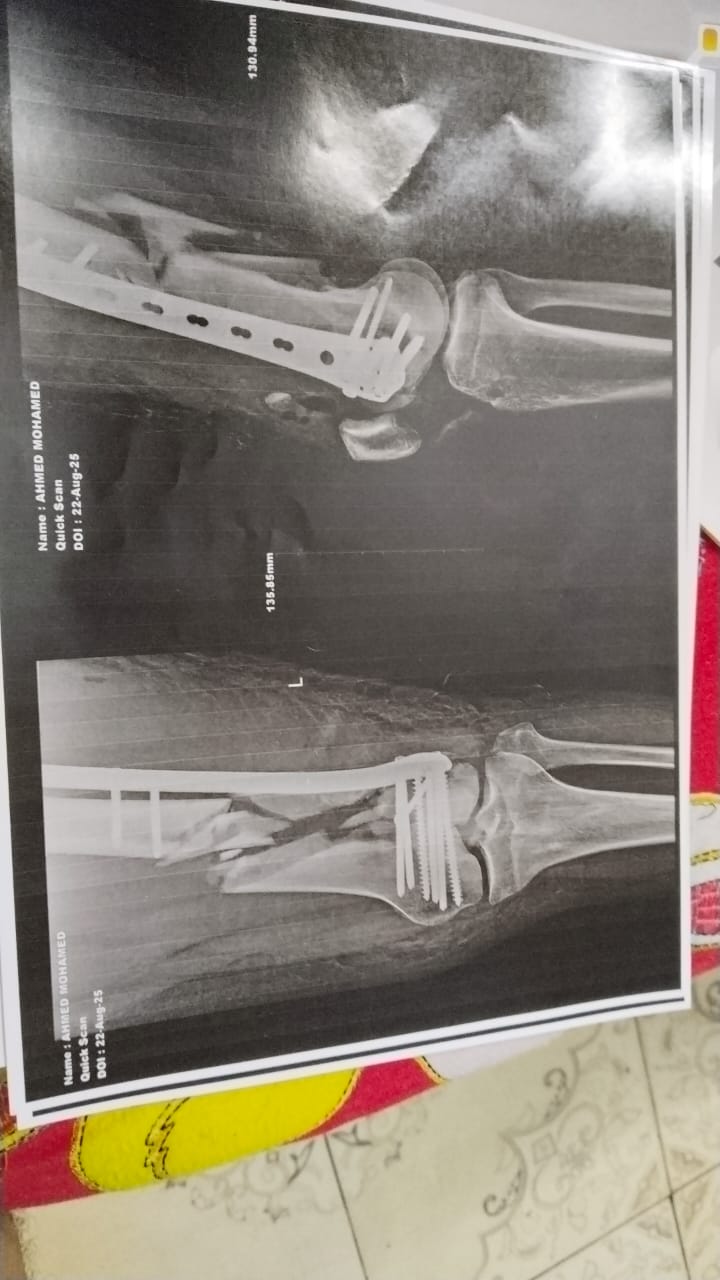

وأضاف أحد مصابي حادث أسيوط، الذي راح ضحيته شخصين وأصيب 31 آخرين، تعرضت لإصابات بالغه نتيجة الحادث، وخضعت لتلقي العلاج بمستشفى الإصابات والطوارئ الجامعي بأسيوط، ولكن تعرضت لخطأ طبي نتيجة الخضوع لإجراء عملية جراحية بالساق.